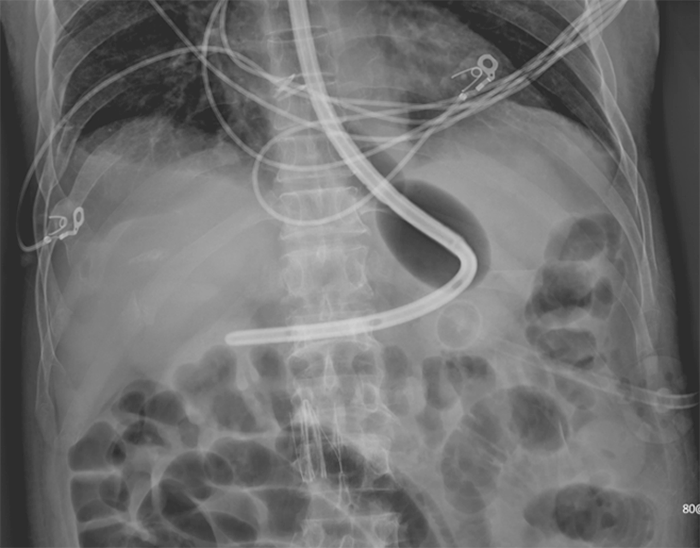

Given the location and nature of bleeding with continued hemorrhagic shock, the decision was made to proceed with esophagogastric balloon tamponade (EGBT). A Minnesota tube (MT; Figure 3) was placed under fluoroscopic guidance. The gastric and esophageal balloons were inflated for 6 hours after radiographic confirmation (Figure 4) then deflated to minimize esophageal ischemia.

The four ports allow inflation of gastric and esophageal balloons as well as gastric and esophageal aspiration. Insertion is performed under fluoroscopic guidance until uninflated gastric balloon is noted to be intragastric. The gastric balloon is serially insufflated to 500 cc with air, not exceeding 15 millimeters mercury (mmHg). The tube is retracted until the gastric balloon is at gastroesophageal junction an secured to helmet on patient's head. The gastric and esophageal aspiration ports are connected to suction at 60-100 mmHg and 120-150 mmHg, respectively. Correct placement is confirmed radiographically. The esophageal balloon is inflated to 40 mmHg and deflated every six hours to reassess for hemorrhage and to limit esophageal ischemia

Figure 4. Abdominal Radiograph with Evidence of Correct Positioning of Minnesota Tube. Published with Permission